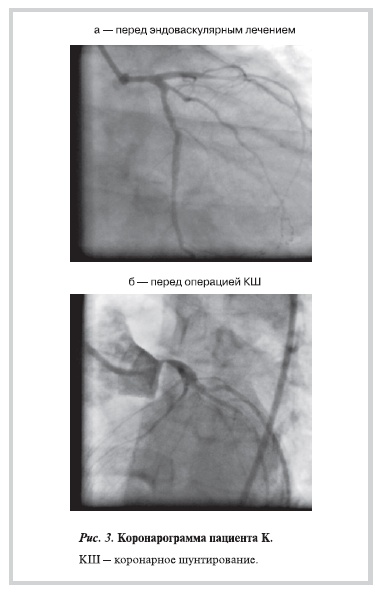

Приводим клинический пример. Пациент К. с диагнозом: ИБС: стенокардия напряжения III ФК,

атеросклероз КА (многососудистое поражение), постинфарктный кардиосклероз (ИМ передней

локализации от 02.06.09), артериальная гипертония. При коронарографии выявлены стенозы ПНА 85%,

АТК 75% и ПКА до 80%. Ангиограмма ПНА и АТК до эндоваскулярного вмешательства представлена на рис. 3, а. 03.07.09 выполнено ЧКВ со стентированием ПНА, АТК, ПКА, установлено 3 стента с лекарственным покрытием. С января 2010 г. возобновились приступы стенокардии, нагрузочный тест — положительный, при повторной коронарографии (рис. 3, б) — стеноз ствола ЛКА 90%, стеноз ПНА в устье 70% (проксимальнее места имплантации стентов).

Критическое поражение коронарного русла, стеноз ствола ЛКА, угроза развития фатального ИМ явились показанием к хирургическому лечению — КШ, которое выполнено 16.03.10 г.: аутовенозное шунтирование ОА + АТК с формированием искусственной Y-образной конструкции, аутовенозное шунтирование ДА, ПКА (после эндартерэктомии), маммарокоронарное шунтирование ПНА (после эндартерэктомии).

Интраоперационно: выраженное протяженное атеросклеротическое поражение всей ПНА и стенозы

проксимальнее места установки стента в ПКА; принято решение о необходимости выполнения

эндартерэктомии. При эндартерэктомии из ПНА удалена атеросклеротическая бляшка длиной 10 см, которая включала тромбированный стент (рис. 4).